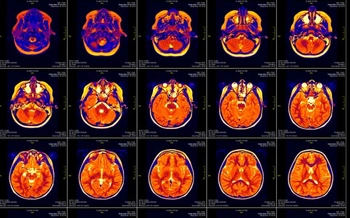

• New MRI Technique Could Expand Treatment Options for Stroke Victims

Scientists from Trinity College Dublin have shown that looking at sodium levels rather than water levels in the brain may offer the potential to extend the time-window during which drug therapy may be given to stroke patients.